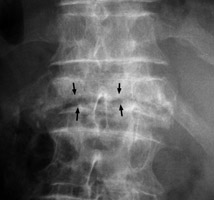

Intravertebral Vacuum Cleft

Avascular Necrosis

Single frontal radiograph of the spine revealing a horizontally oriented linear area of lucency within the body of a single collapsed vertebral body. The intravertebral vacuum cleft sign is a gas-density cleft with a transverse separation of the vertebral body, appearing in extension and disappearing in flexion. It is secondary to local bony ischemic necrosis with nonhealing vertebral collapse. This ischemic vertebral fracture is not known to occur secondary to inflammation or neoplastic causes.